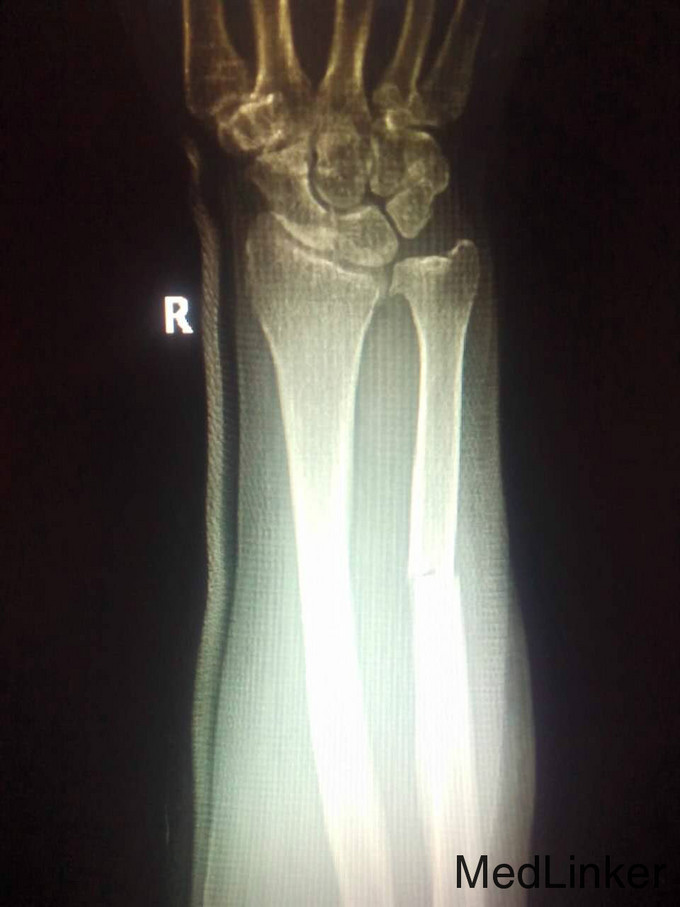

右尺挠骨骨折

叶海珍 女 62岁 右上肢肿痛3小时,患者于3小时前不慎伤及右上肢,伤后伤处疼痛活动受限,查:局部胀痛,无畸形,末端感觉皮温正常,诊断右尺挠骨折,为求一步治疗来我院。X提示右尺挠骨骨折。